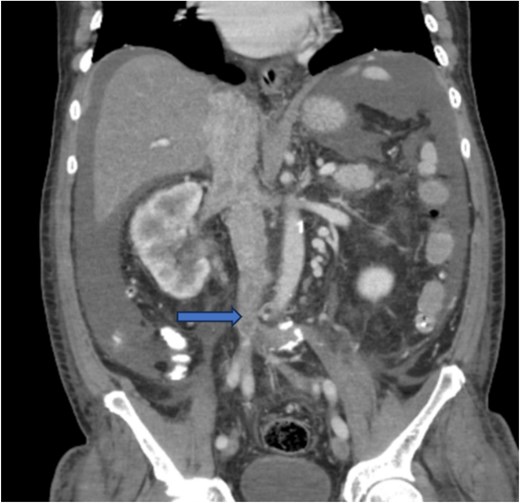

Diagnostic imaging began with a chest X-ray that indicated bilateral pleural effusions. An abdominal ultrasound detected a 4.6 × 4.2 × 4.3 cm echogenic lesion in the right hepatic lobe. Further imaging with a computed tomography (CT) scan of the chest, abdomen, and pelvis revealed a large mass originating from the posterior aspect of the right mid-kidney consistent with RCC (Fig. 1). The mass associated with thrombus extended into the renal sinus and collecting system, traveled along the right renal vein to the inferior vena cava (IVC), and projected into the right atrium (Figs 2 and 3). During hospitalization, bilateral lower extremity pain led to the diagnosis of bilateral deep vein thromboses via duplex venous ultrasound. Echocardiography showed normal left ventricular ejection fraction, impaired diastolic filling, mildly increased ventricular wall thickness, and an echogenic mass extending from the right atrium into the IVC consistent with the tumor thrombus.

CT chest abdomen and pelvis with contrast showing inferior extension to the level of the distal margin of the IVC.